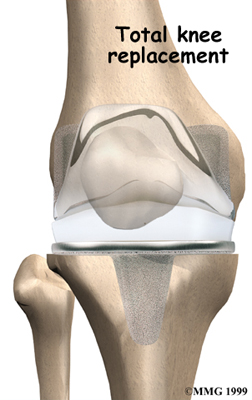

Artificial Knee Replacement

An artificial knee replacement is the ultimate solution for advanced knee OA.

Surgeons prefer not to put a new knee joint in patients younger than 60. This is because younger patients are generally more active and might put too much stress on the joint, causing it to loosen or even crack. A revision surgery to replace a damaged prosthesis is harder to do, has more possible complications, and is usually less successful than a first-time joint replacement surgery.

Related Document: FYZICAL Raleigh's Guide to Artificial Joint Replacement of the Knee